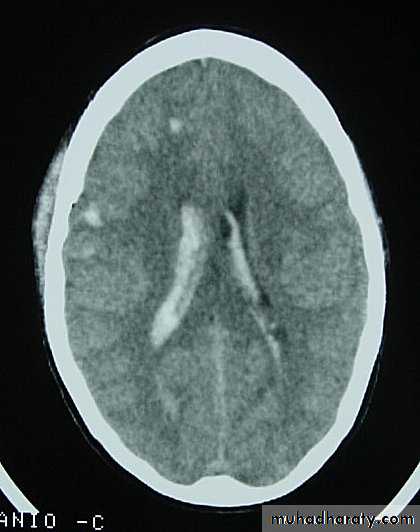

CT scans demonstrates contusions as small areas of haemorrhage in the cerebral parenchyma.

Contusions may resolve with the accompanying deficits or they may persist.

3. Cerebral Contusion

Neurosurgery